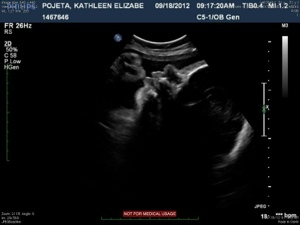

The next four images just show various views of the strands/septations that are visible within the sac.

20120921-213522.jpg